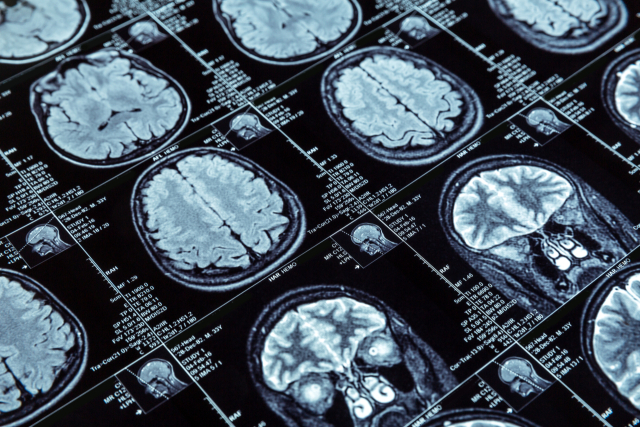

23일 질병관리청 국립보건연구원은 혈당과 혈압의 변화가 크지 않도록 관리하면 인지 기능 저하를 막아 치매를 예방할 수 있다는 연구 결과를 발표했다. 당뇨와 고혈압은 대표적인 치매 위험 인자로 알려져 있지만, 수치뿐 아니라 변동성도 치매와 관련이 있다는 의미다.

서상원 삼성서울병원 신경과 교수는 노인성 치매 환자 코호트 분석에서 치매가 없는 2600여 명을 대상으로 6년간 혈당과 혈압의 표준 편차를 계산한 결과 혈당 변동성과 혈압 변동성이 알츠하이머병 지표와 혈관성 치매 지표에 영향을 미친다는 것을 확인했다.

연구 결과 혈당 변동성이 증가할수록 심한 대뇌 백질의 변성이 발생했고, 아밀로이드 단백질의 축적이 증가했다. 대뇌 백질 변성은 뇌의 백색질에 손상이 발생한 상태로, 혈관성 치매의 지표이고, 아밀로이드 단백질은 알츠하이머 치매 환자의 뇌에서 발견되는 치매 유발 물질이다.

혈압 또한 수축기와 이완기의 혈압이 오르락내리락하는 변동성이 클수록 타우 축적이 증가하고, 이완기 혈압의 변동성이 클수록 뇌 해마 위축이 심화되는 것으로 나타났다.

연구팀은 혈압 변동성이 뇌의 혈류을 불안정하게 만들어 세포 사멸을 일으키는 주요 원인으로 알려진 타우의 축적을 촉진하고, 해마를 포함한 뇌 구조에 손상을 준다고 설명했다.